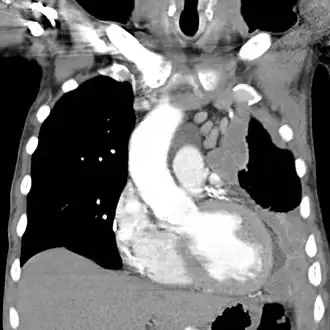

![]() Tomografía Computarizada: Mesotelioma del lado izquierdo con la ampliación ganglionar mediastínica. | ||